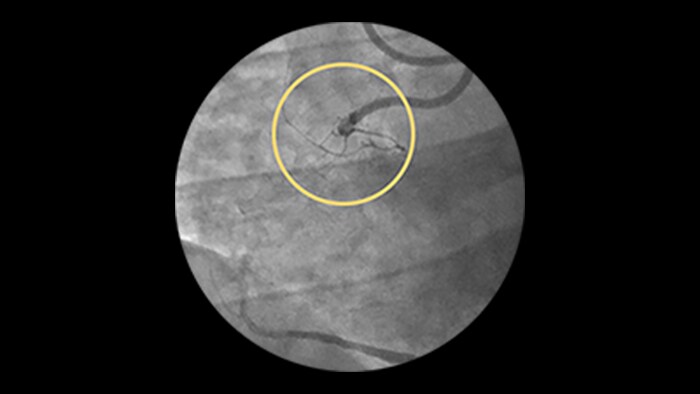

Saphenous vein graft and thrombus lesions

Advanced tools for optimal PCI outcomes